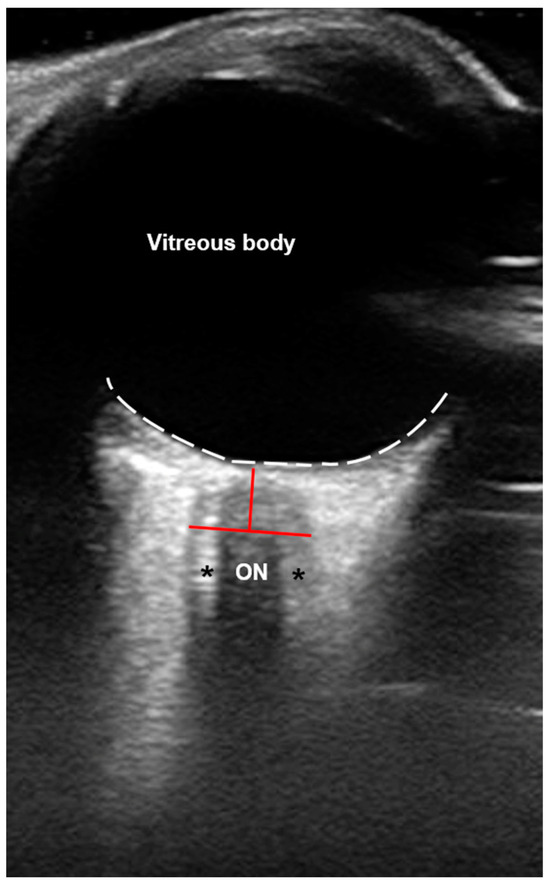

2.3. US Investigation

- Kerscher, S.R.; Zipfel, J.; Groeschel, S.; Bevot, A.; Haas-Lude, K.; Schuhmann, M.U. Comparison of B-Scan Ultrasound and MRI-Based Optic Nerve Sheath Diameter (ONSD) Measurements in Children. Pediatr. Neurol. 2021, 124, 15–20. [Google Scholar] [CrossRef] [PubMed]